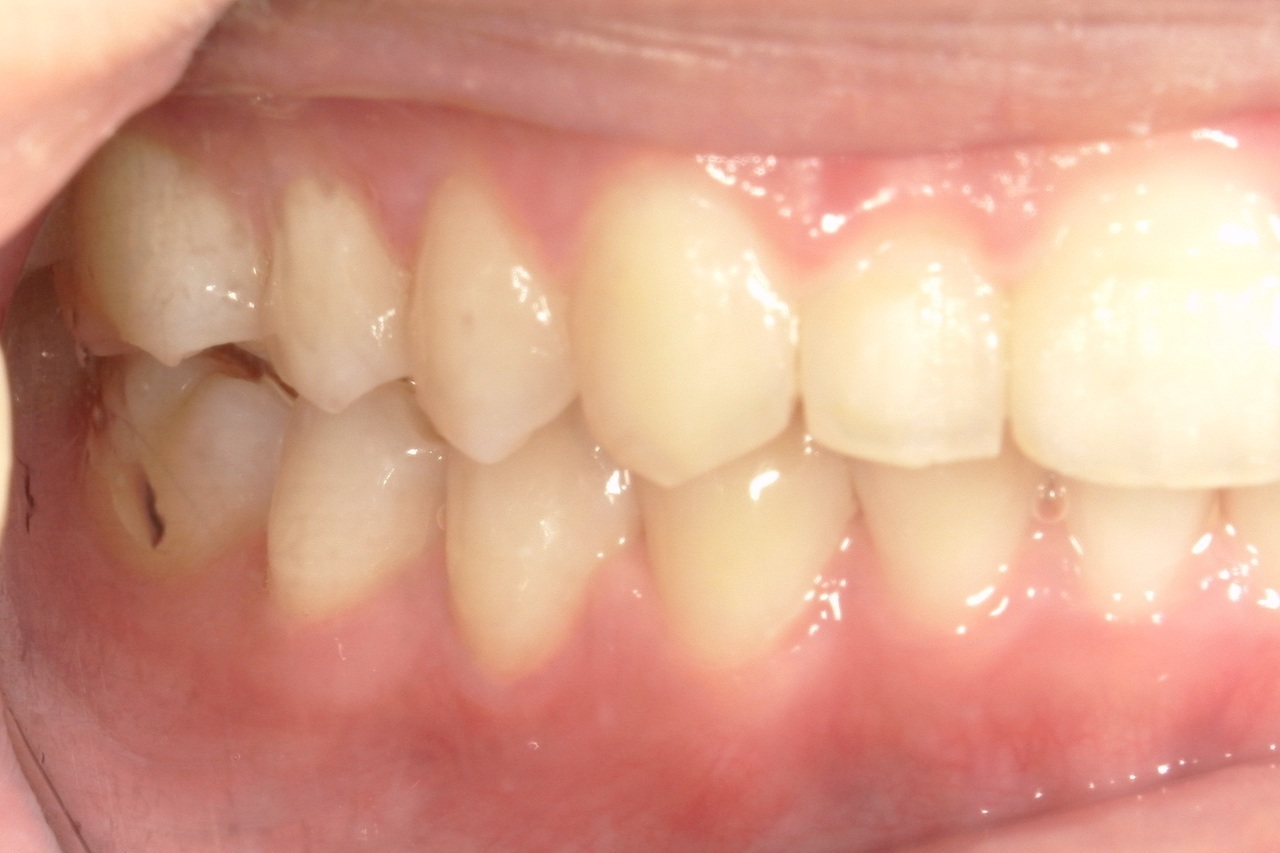

Before

浜松市中央区・自動車学校前駅のインビザラインの症例

Y.S. 30代男性

全体的にガタガタしているのが気になるという主訴だったため、上下左右第一小臼歯を抜歯し、叢生を並べました。

治療の期間:R3. 9/1〜R5. 10/31

治療の価格:88万円